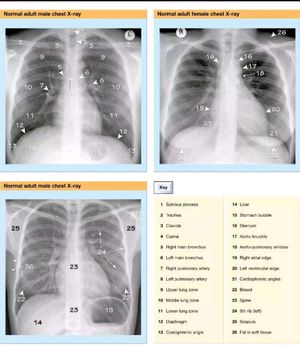

Chest X-Rays